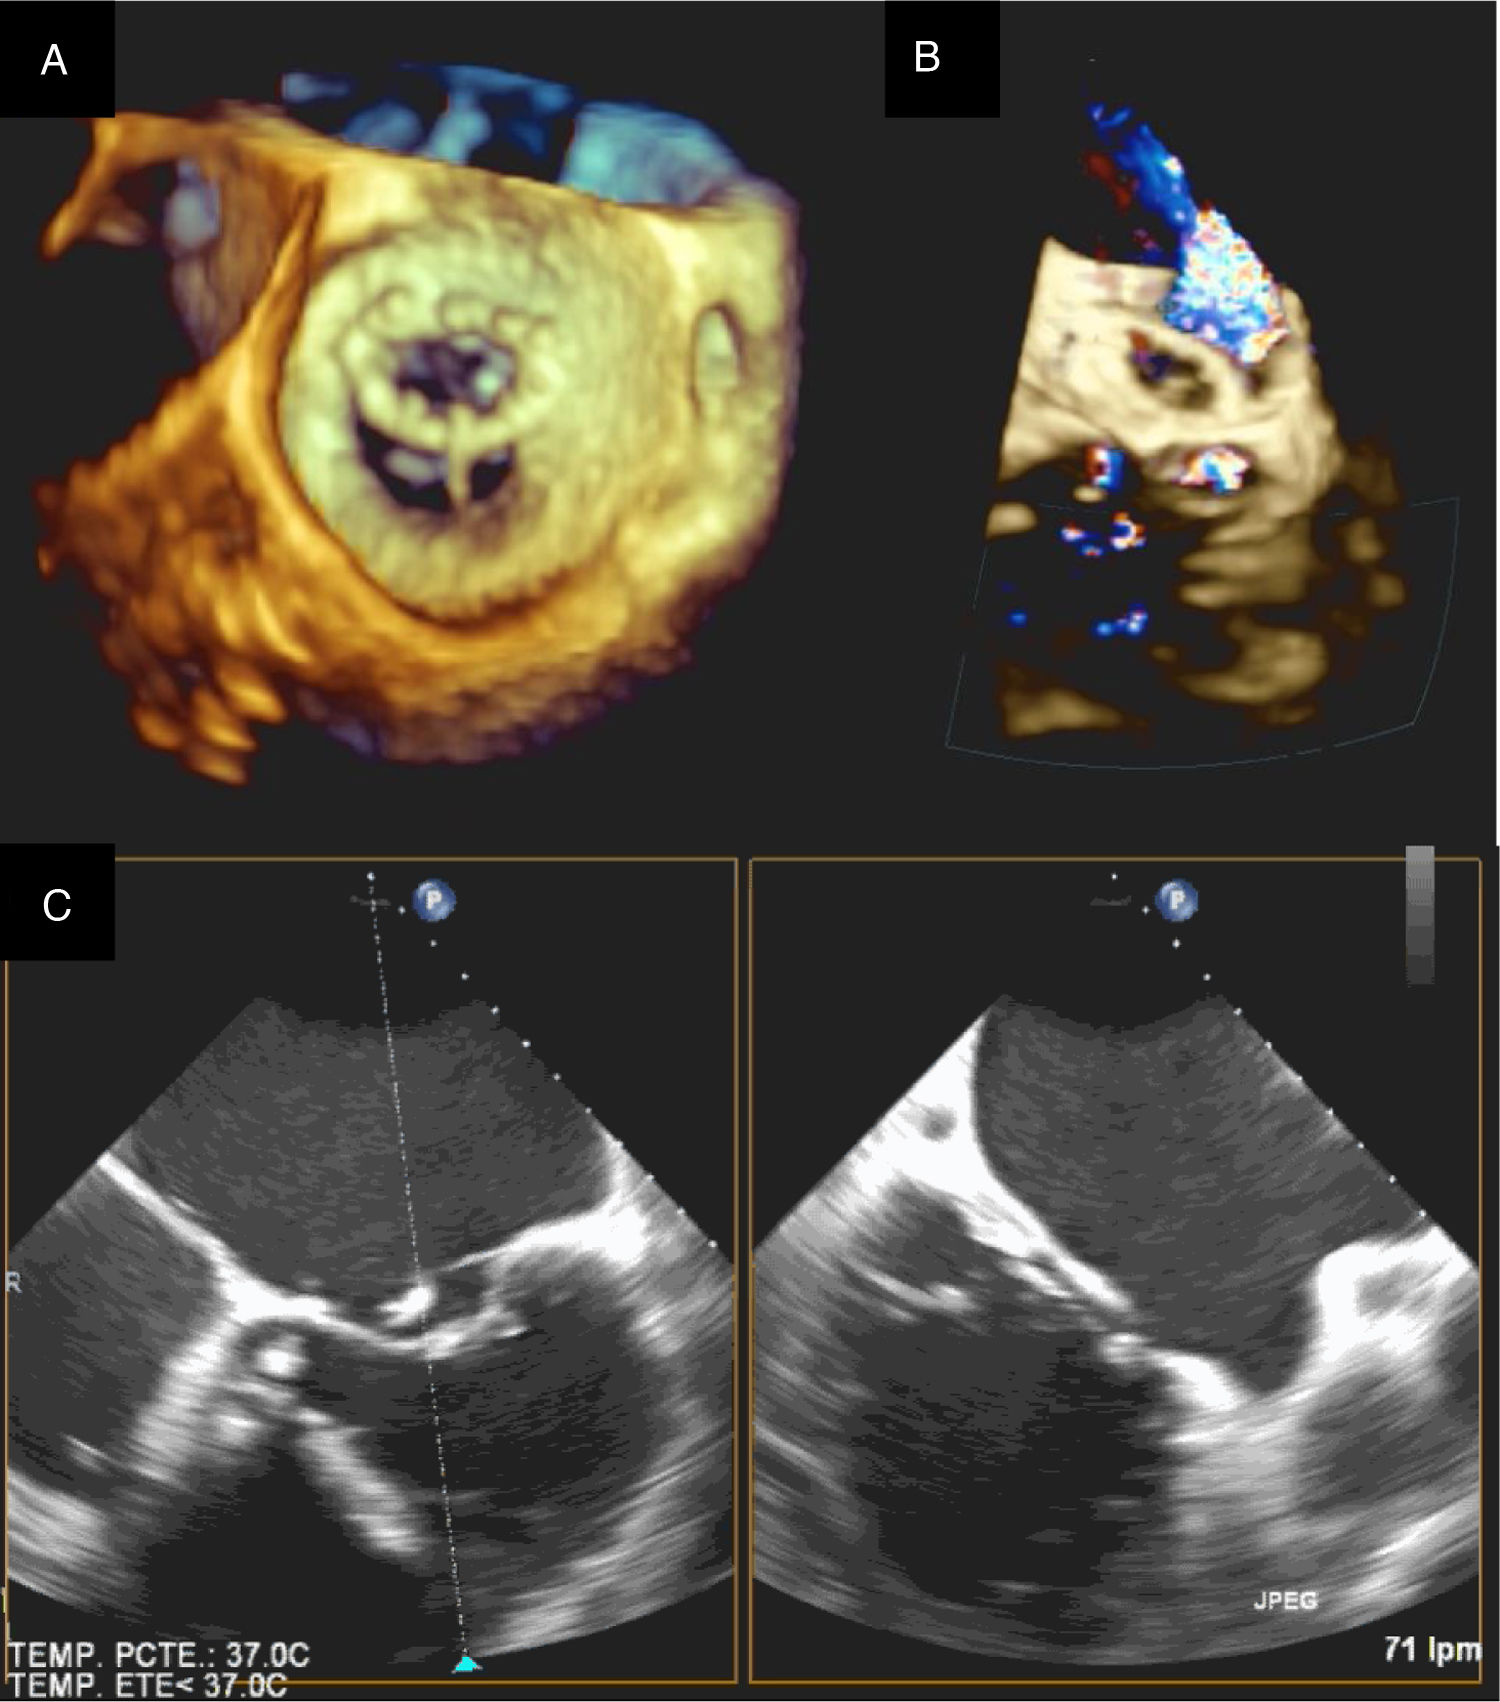

El segundo paciente fue un adulto de 66 años, operado en la infancia de un cierre de la comunicación interauricular. Presentaba una alta incidencia familiar de cardiopatía congénita sin aislamiento de un sustrato genético. Tenía una IM grado iv por restricción del velo posterior con un anillo mitral de 64mm y una IT grado ii con anillo tricuspídeo de 47mm. Se realiza una plastia mitral con anillo de CG Future® de 36mm (Medtronic) con implante de neocuerda en segmento A1 y una anuloplastia tricuspídea con anillo Contour 3D® de 36mm (Medtronic). Presenta bloqueo auriculoventricular completo en el postoperatorio inmediato, por lo que se implanta un marcapasos definitivo al sexto día postoperatorio. A las 24h de la intervención se realiza un cateterismo de urgencia por infarto postoperatorio. Se objetiva acodamiento de la coronaria derecha debido a un punto del anillo tricúspide. Dado que la repercusión solo era bioquímica, sin alteración en la contractilidad, se decide tomar una actitud conservadora y el paciente evoluciona de manera satisfactoria. No obstante, a los 20 días de la intervención el paciente presenta de manera súbita disnea y ortopnea. Se objetiva dehiscencia de la porción posterior del anillo mitral (fig. 1), por lo que se interviene de urgencia implantando una prótesis mitral mecánica Carbomedics® 31mm.

El futuro de la cirugía de reparación valvular múltiple en los pacientes con cardiopatía congénita es incierto. Hay debate sobre el material y las técnicas a emplear. Idealmente no hay que emplear material protésico que degenera con el tiempo y no crece, e intentar trabajar con el tejido autógeno siempre que sea posible. En nuestro caso, ha sido frecuente emplear varias técnicas distintas para reparar una misma válvula5,6,12,14. Este tipo de reparaciones difiere de los cánones habituales de la reparación de valvulopatías adquiridas. En el caso de los defectos de los cojinetes endocárdicos, habitualmente no empleamos anillos protésicos para la válvula mitral. Los defectos de este estilo se corrigen bien cerrando el cleft mitral y a veces es preciso asociar una comisuroplastia. La arquitectura de las válvulas auriculoventriculares de estos pacientes está alterada, y comparado con la anatomía habitual, un anillo protésico distorsiona la plastia mitral15,16. El abordaje cambia cuando la etiología de la valvulopatía mitral es una displasia primaria no asociada a defecto del septo auriculoventricular; aquí la reparación es más compleja, requiriendo diversas técnicas para conseguir una buena coaptación de los velos. En este tipo de pacientes sí es necesario asociar un anillo mitral para consolidar la reparación, siempre y cuando el tamaño del paciente nos lo permita (fig. 2). En la válvula tricúspide se emplea más libremente el anillo o, en su defecto, una plastia de Vega cuando el paciente es pediátrico. En el caso de la válvula aórtica recomendamos afeitado de velos y apertura de comisuras en válvulas estenóticas para ganar movilidad, aunque el arsenal terapéutico para anillos pequeños es más limitado (fig. 3). En los casos de insuficiencia aórtica se hará plastia de velos para evitar que estos prolapsen y logren una buena altura de coaptación, y si esta se asocia a dilatación aneurismática de la raíz aórtica se realizará técnica de David. Cuando la valvuloplastia convencional no es suficiente hay que explantar la válvula, teniendo como principal opción el Ross en lactantes y niños pequeños. Nuestra experiencia inicial con la técnica de Ozaki (reconstrucción de neovelos aórticos) es buena y puede tener un papel en los candidatos que requieran la reparación de 2 o más válvulas13.